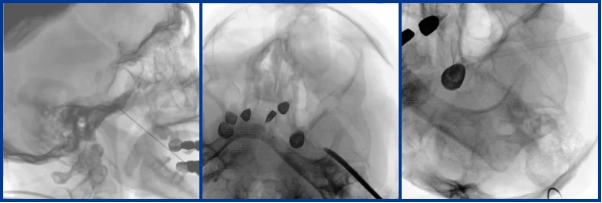

Integrated C-Arm with a Large FPD Assists Pain Management Department in Performing Spinal Cord Stimulation Implantation

Mobile Flat-Panel C-Arm Supports Trigeminal Ganglion Balloon Compression Surgery

Operating rooms often have confined spaces and need to accommodate auxiliary equipment such as ozone and radiofrequency machines. Perlove's mobile C-arm with FPD, with its compact design and high mobility, can be easily positioned and moved within these limited spaces, making it a standard configuration for any pain management department.

Perlove Medical’s mobile flat-panel interventional C-arm meets the needs of most interventional procedures. For complex pain treatments, such as vascular interventions and tumor-related pain management, its real-time dynamic imaging and wide field of view offer comprehensive intraoperative imaging support throughout the entire procedure.